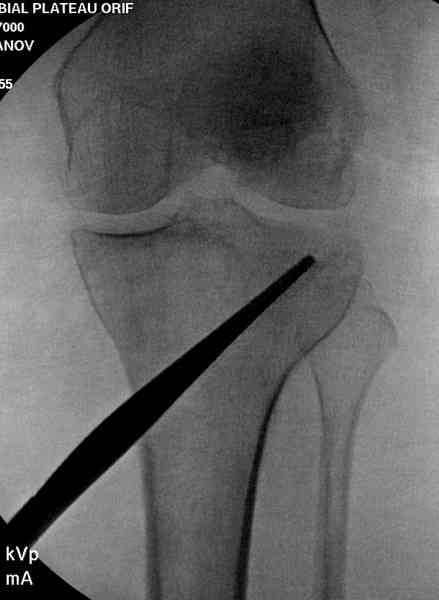

Из медиального окна можно приподнять латеральную

импрессию. Фиксация тремя параллельными шурупами в

эпифизарной части над импрессией. Создается крыша,

которая предупредит коллапс. На образовавшуюся полость - костная пластика из аутокости или синтетический заменитель. Мы применяем Osteoset в 4-5 мм диаметре таблеточки или иньекционную форму Prodens.

Медиально, обычно на протовоположной

строне, делается окно в кортикальном слое, кривым забойником под рентгеном поднимается импрессия.

После заполнения образовавшейся полости в метафизе

кортикальное окно можно прикрыть.

Это техника применяется, когда имеется

центральная импрессия, а при ипрессии с краевым переломом - после приподнимания импрессии опорная (Butress) пластина, как на снимке.